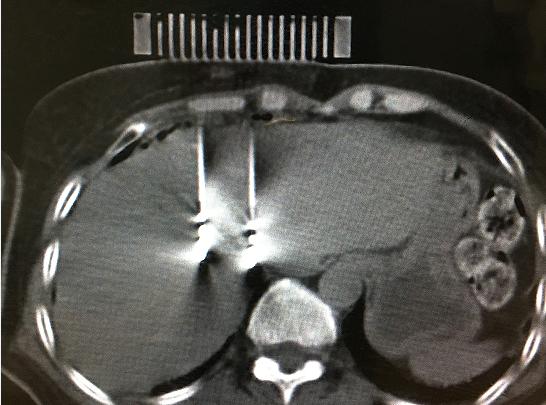

9月11日,醫(yī)院腫瘤科張開賢主任醫(yī)師團隊對一例肝癌術后復發(fā)的患者成功進行了國內首例3D打印共面模板引導下的微波消融術,標志著肝癌進入精準微波消融時代。

患者女性,57歲,肝癌術后5月復發(fā),病灶6.0cmx6.0cm大小,位于肝臟的右葉,靠近隔頂部,經(jīng)過多學科討論,決定實施經(jīng)皮微波消融術,由于腫瘤體積較大,需要同時使用兩根消融天線進行多平面消融,為確保療效,兩根消融天線需要平行等距,但由于肝臟是不斷運動的臟器,徒手操作有一定技術難度,往往需要多次穿刺調整進針方向才能達到上述要求,為此,滕州市中心人民醫(yī)院腫瘤科張開賢主任醫(yī)師團隊借鑒既往采用模板引導放射性粒子植入的經(jīng)驗,創(chuàng)造性地將3D打印模板技術應用于該例患者的消融治療,在模板引導下在兩個平面上平行等距插入兩根消融天線,經(jīng)過18分鐘的消融,腫瘤完全壞死,達到完全消融,患者正在術后康復之中。

3D打印模板引導消融的優(yōu)點:迅速將腫瘤與模板“固定”,防止因肝臟運動導致的穿刺不確定性;確保兩根消融天線平行等距,使熱場分布更加均勻;一次性穿刺布針成功,避免反復穿刺導致的腫瘤種植性轉移;模板對消融天線起到固定,防止因來回移動導致的消融天線位置的改變。據(jù)悉,這是國內首例3D打印模板引導下的肝癌微波消融術,這一技術的推廣應用必將造福更多的腫瘤患者。(腫瘤一科 胡苗苗)